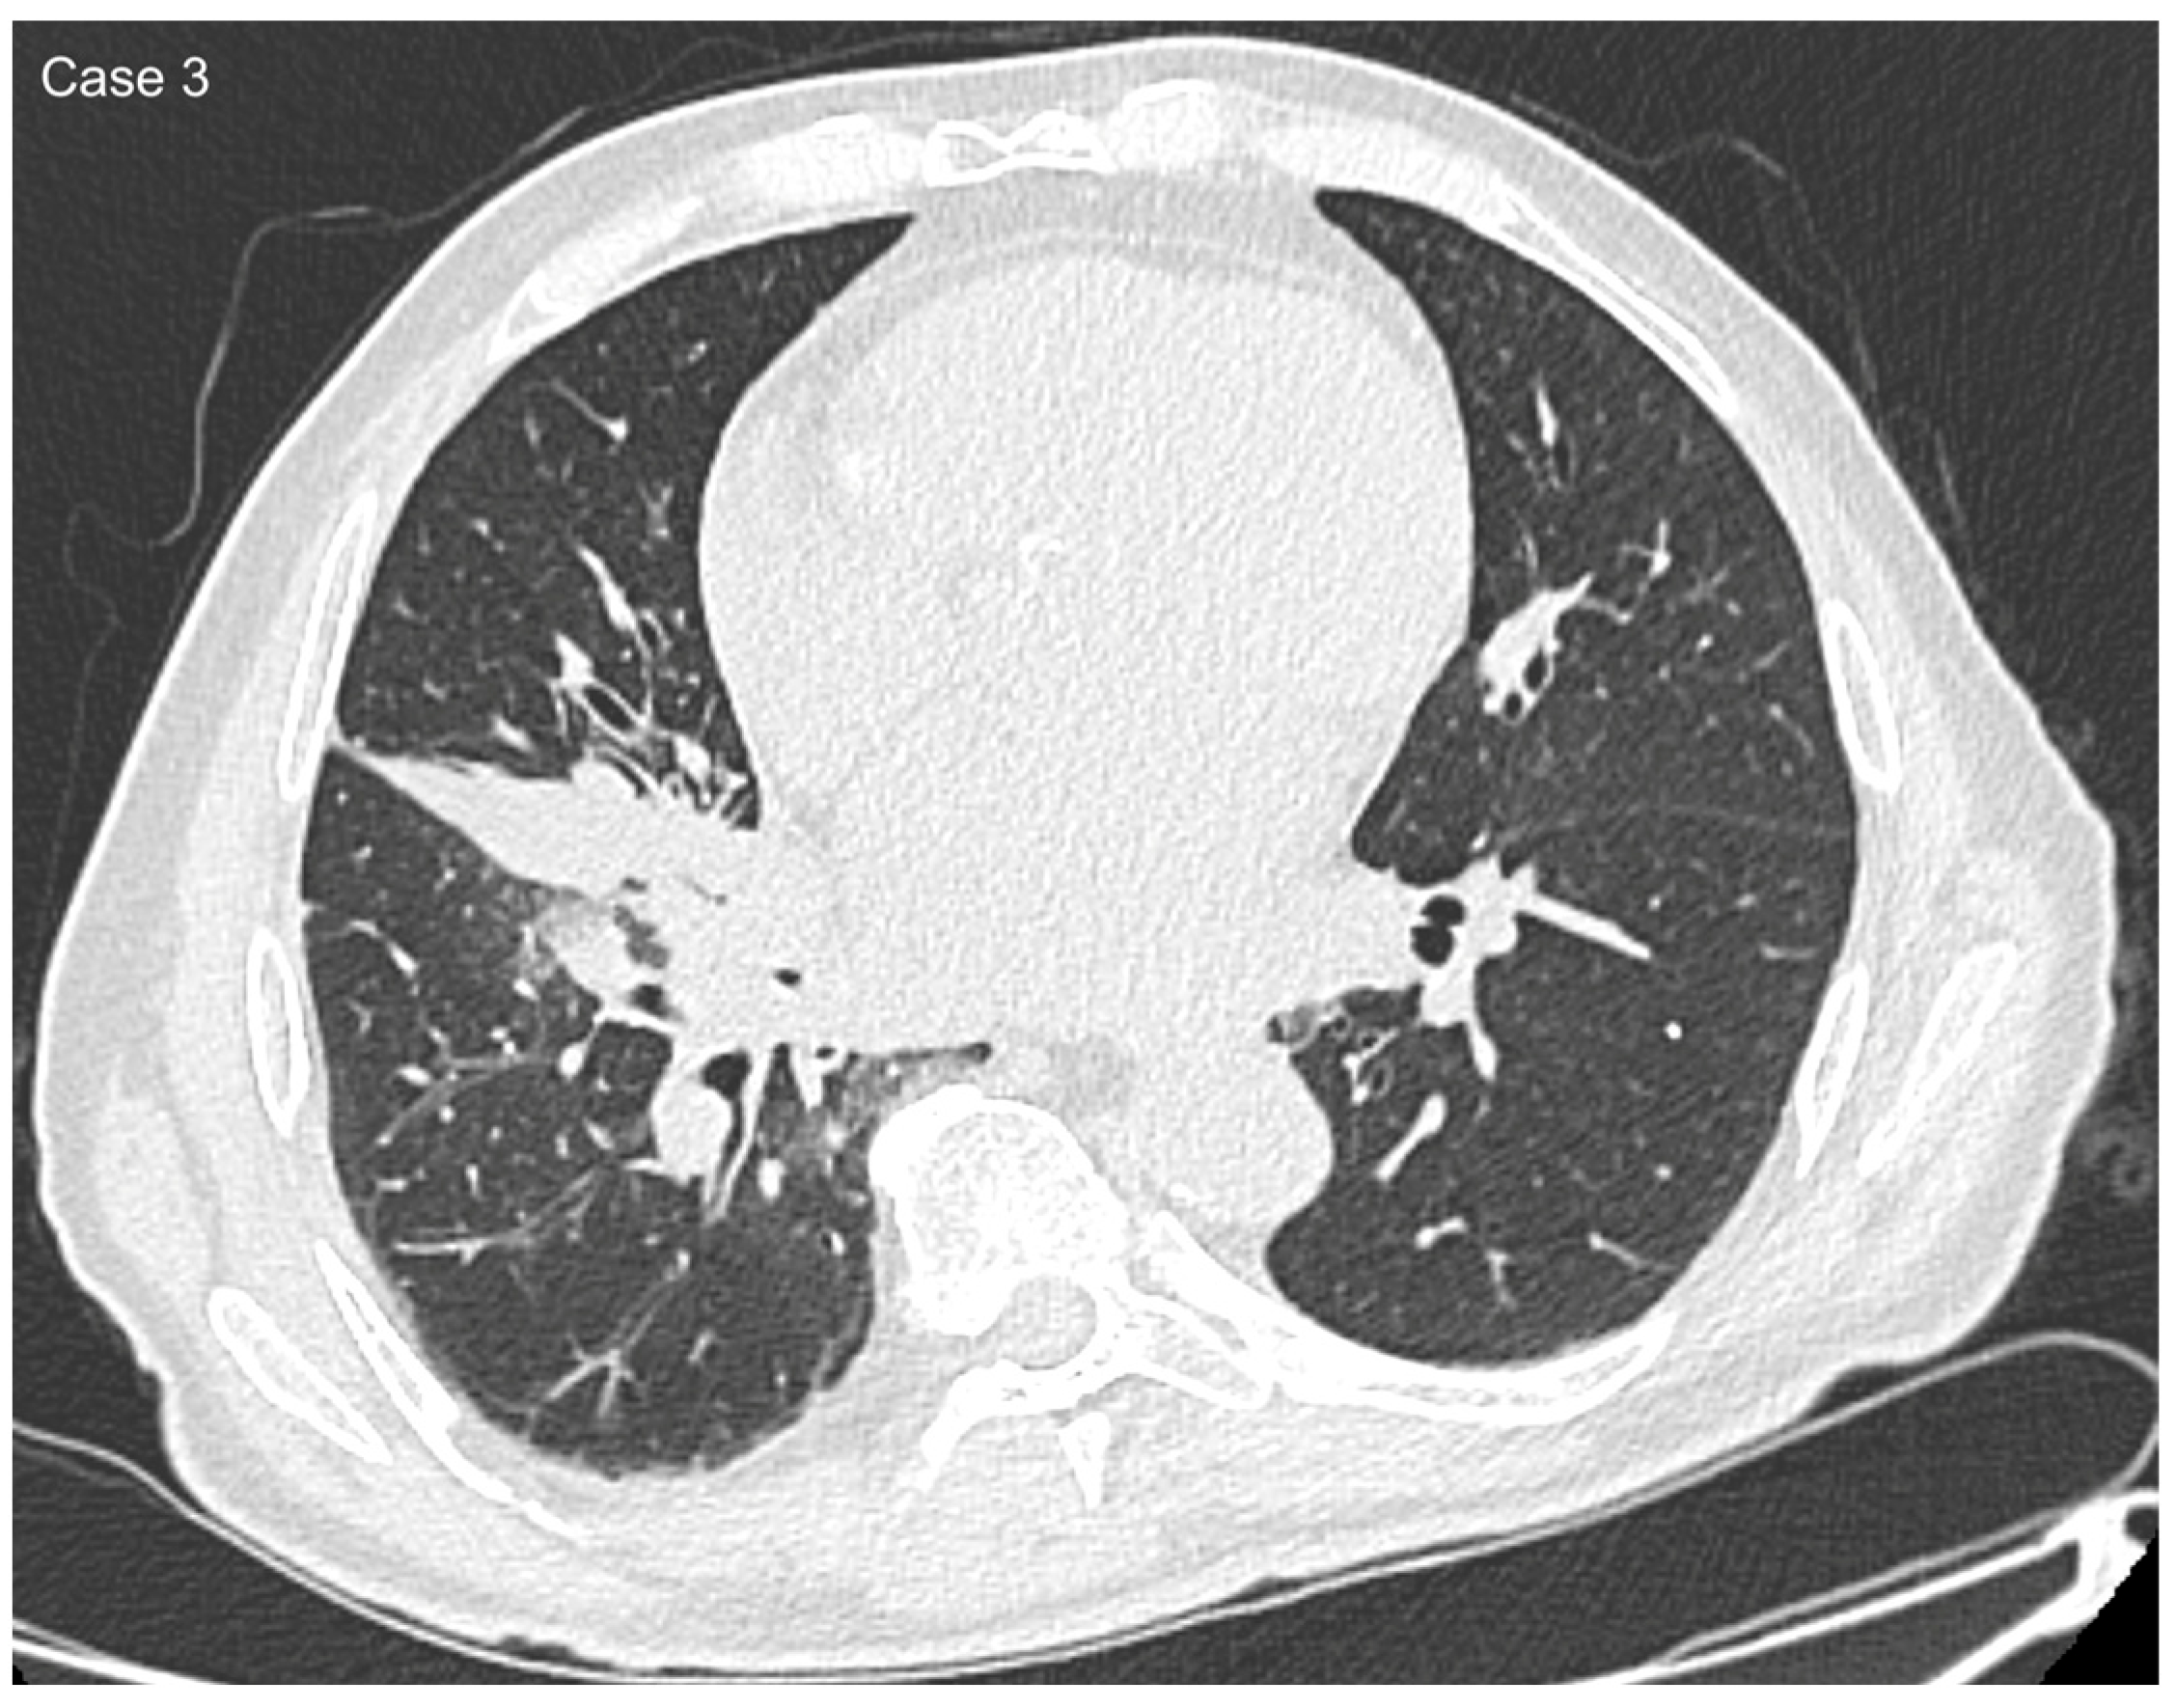

| Imaging features | Spiculated margins: 88% Central necrosis: 38.4% Cavity: 10.4% Lymphangitic spread: 43.2% |